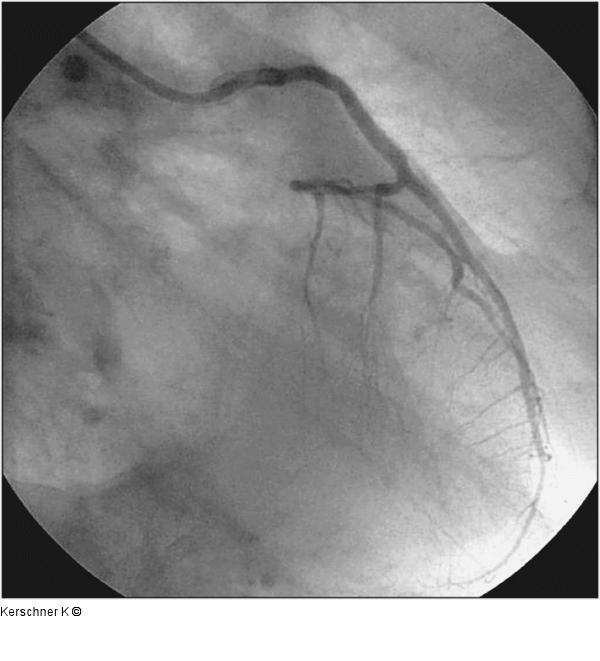

Abbildung 7: Kissing-Ballon - RAO-Projektion Endergebnis nach Kissing-Ballon - RAO-Projektion |

Endergebnis nach Kissing-Ballon - RAO-Projektion |